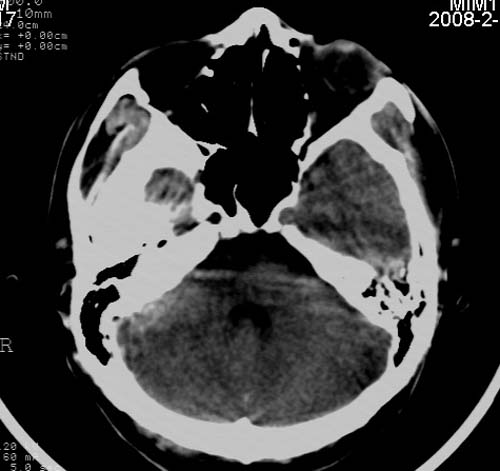

男,17岁,3天前与人斗殴,自述头痛、头晕。无恶心、呕吐,无阳性体征,一般情况良好。

其内似可见脂肪密度影,考虑畸胎瘤可能性大.

病灶以钙化为主,无明显占位效应,病灶周围无水肿,这种情况应该是脑血管畸形,最多见的是动静脉畸形,其次是海绵状血管瘤.

病人较年轻,有头疼、头晕症状,动静脉畸形可能性大。